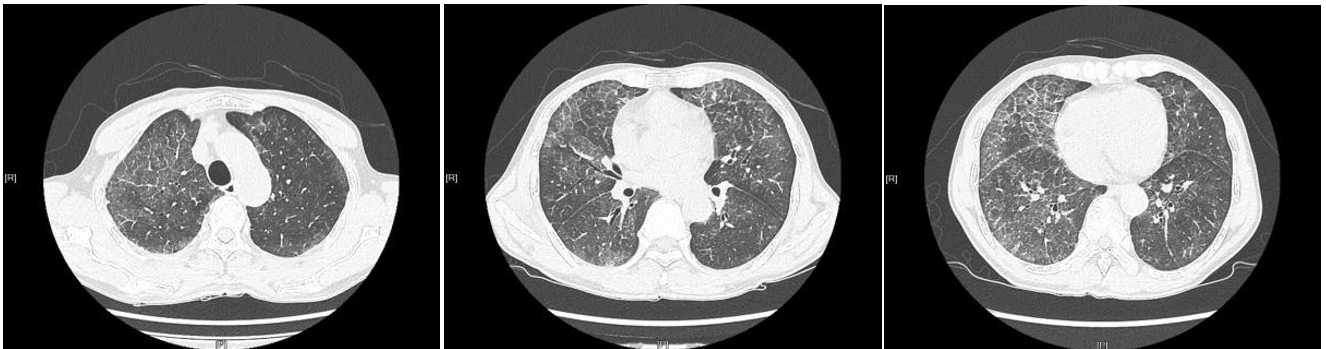

治疗前胸部CT:两肺多发磨玻璃阴影,典型的铺路石症